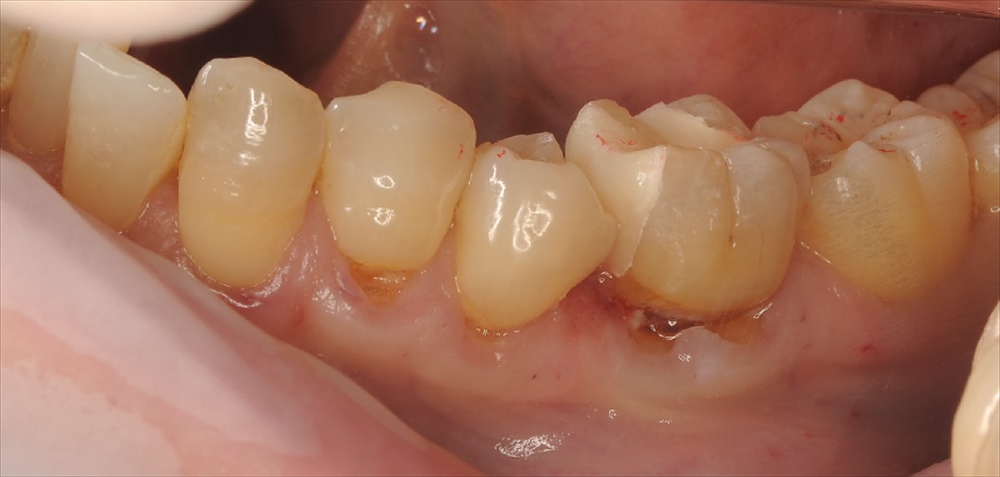

6ヶ月後

の本日

全くしみなくなったと笑顔でした、私も嬉しい!!ここからこの歯の仮歯を本物に変えていきます。